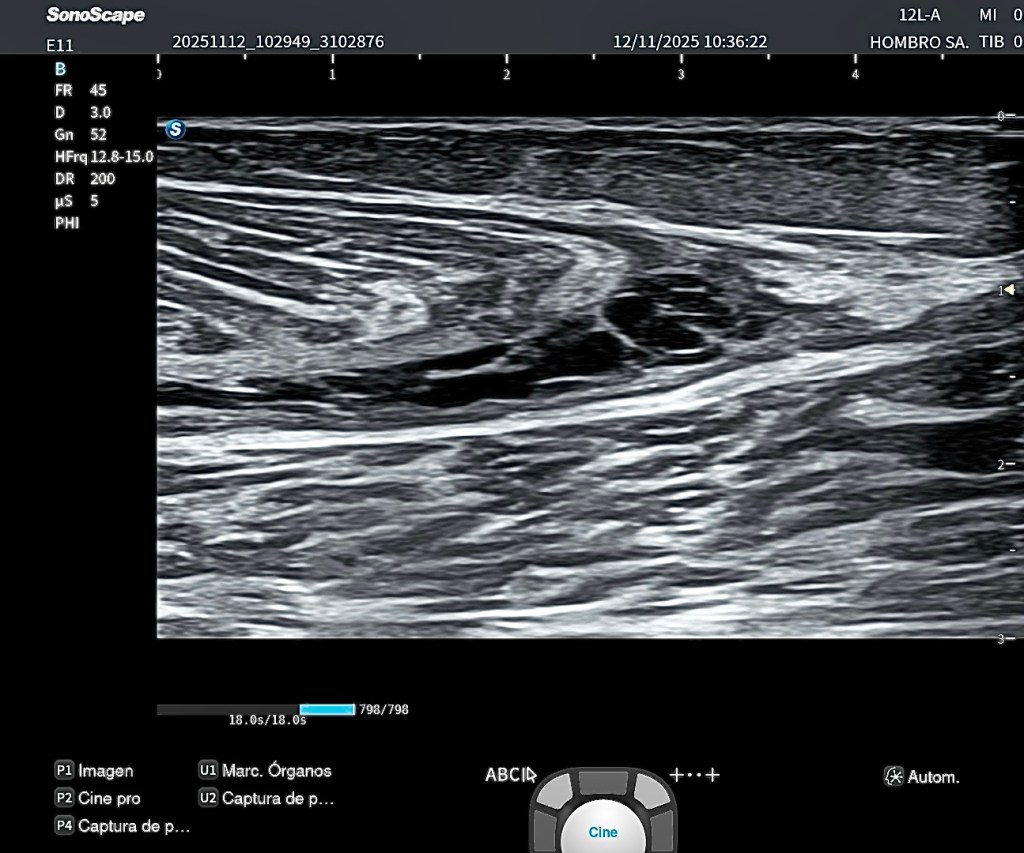

El estudio ecográfico longitudinal y transversal del compartimento posterior superficial muestra:

- Presencia de hematoma intermuscular parcialmente organizado, con septos internos bien definidos que indican fase no aguda del proceso.

- Retracción parcial del vientre muscular del gastrocnemio medial.

- Panoramic View se observa la longitud y extensión de la zona afecta